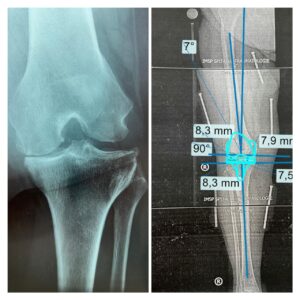

Importanța planificării preoperatorii

Medicul subliniază că fiecare intervenție este planificată individual, pentru a reduce riscurile și a obține cele mai bune rezultate. Planificarea preoperatorie presupune:

- poziționarea corectă a implantului;

- determinarea fenotipului genunchiului și a gradului de uzură;

- reducerea erorilor intraoperatorii;

- diminuarea sângerării și a complicațiilor postoperatorii.

Totodată, succesul intervenției depinde în mare măsură de respectarea anatomiei individuale a pacientului și de restabilirea funcționalității genunchiului.